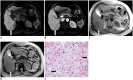

During chemotherapy in patients with gastrointestinal malignancy, the hepatic lesions may occur as chemotherapy-induced lesions or tumor-associated lesions, with exceptions for infectious conditions and other incidentalomas. Focal hepatic lesions arising from chemotherapy-induced hepatopathies (such as chemotherapy-induced sinusoidal injury and steatosis) and tumor-associated eosinophilic abscess should be considered a mimicker of metastasis in patients with gastrointestinal malignancy. Accumulating evidence suggests that chemotherapy for gastrointestinal malignancy in the liver has roles in both the therapeutic effects for hepatic metastasis and injury to the non-tumor bearing hepatic parenchyma. In this article, we reviewed the updated concept of chemotherapy-induced hepatopathies and tumor-associated eosinophilic abscess in the liver, focusing on the pathological and radiological findings. Awareness of the causative chemo-agent, pathophysiology, and characteristic imaging findings of these mimickers is critical for accurate diagnosis and avoidance of unnecessary exposure of the patient to invasive tissue-based diagnosis and operations.

- Han NY, Park BJ, Sung DJ, Kim MJ, Cho SB, Lee CH, et al. Chemotherapy-induced focal hepatopathy in patients with gastrointestinal malignancy: gadoxetic acid--enhanced and diffusion-weighted MR imaging with clinical-pathologic correlation. Radiology. 2014;271:416–425. - PubMed